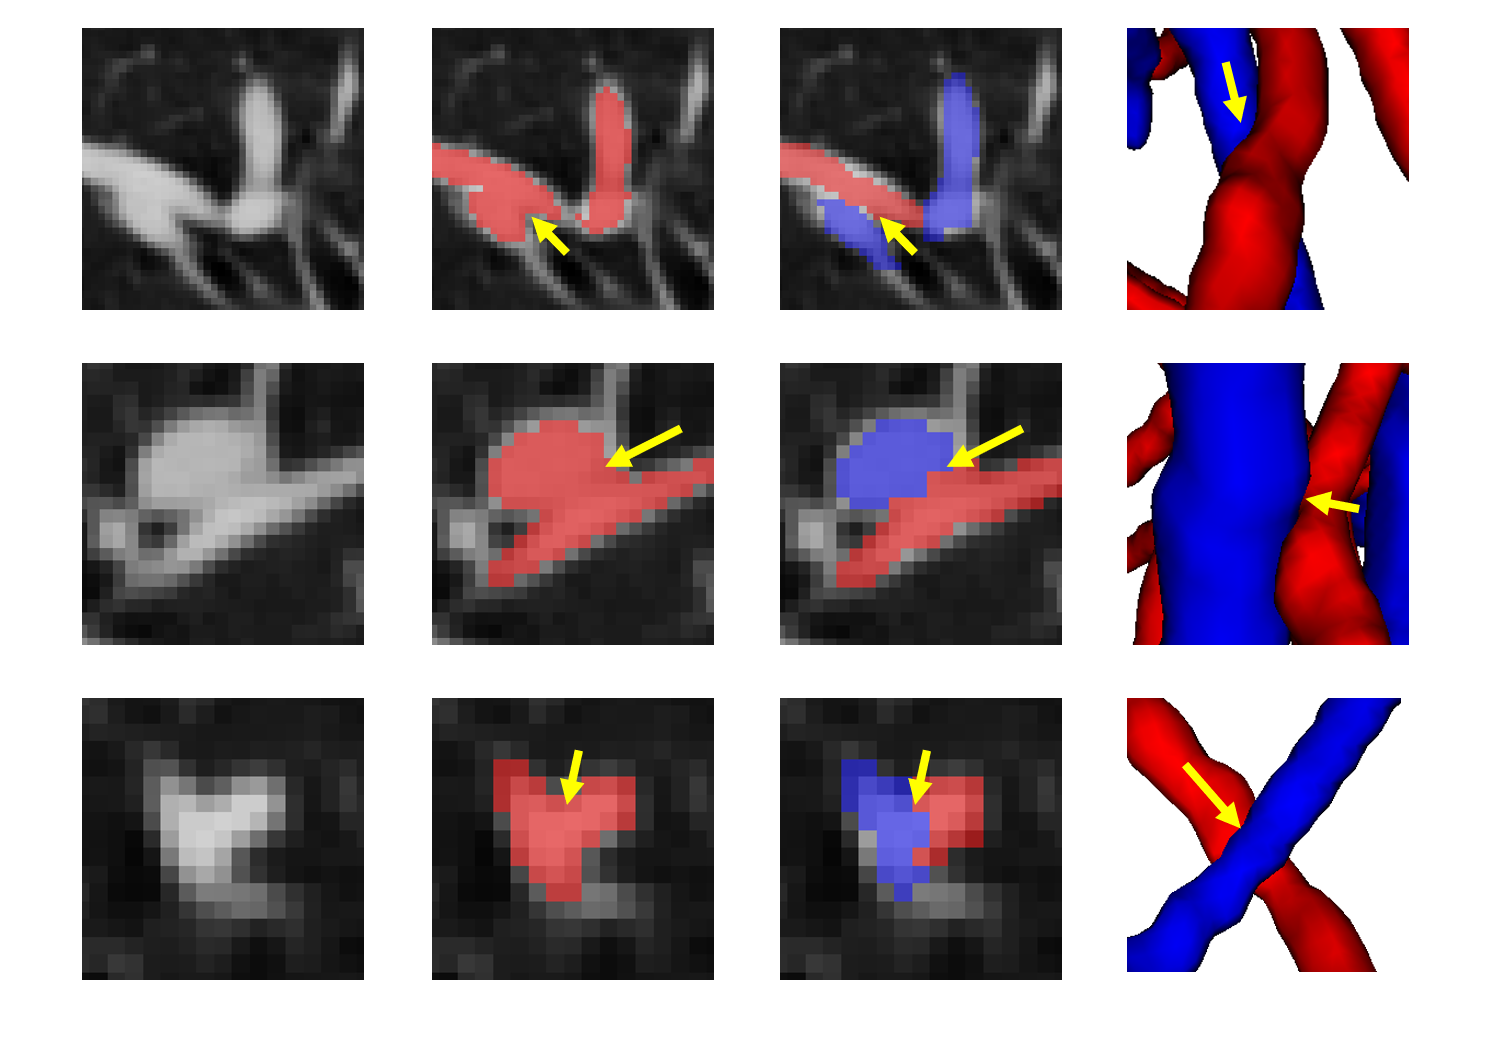

Finally, the topology optimizer extracts the topology subtree and topology branch refinement results by the method in Section 2.3. The results of a topology subtree and topology branch are shown in Fig. 9. Then, we use topology subtrees and topology branches for postprocessing. As shown in Table 3, the proposed topology optimizer is superior to the subtree-based and branch-based topology optimization in accuracy. Fig. 14 and 15 show the reconstructed results of different topology strategy optimizers. The results in Fig. 14 show that when the number of points on the branch is small, and the branch-based topology optimization method is prone to predict errors. This finding is mainly because the branch-based refinement strategy focuses on the relationships within the branches and ignores the topological relationships between branches. As shown in Fig. 15, topology optimization based on subtree strategy is prone to prediction errors in the case of arterial-vein intersection. This finding is mainly because the arterial/venous intersection point in the extraction process of topological subtree is easily mistaken for the bifurcation point of arterial subtrees due to the complex structure of the vascular tree, arteries and veins interweave, and finally the venous branches are classified as arterial subtrees, resulting in the classification error.

Fig. 16 shows the final separation result of our method at the intersections of the arteries and veins. The proposed topology optimizer considers the interbranch and intrabranch relationships. The extracted topological subtree is used to maintain the spatial connectivity of topological particles. The branch confidence calculated using topological branches is used to correct the topological subtree. To some extent, our method can solve the misclassification problem caused by interlaced arteries and veins.